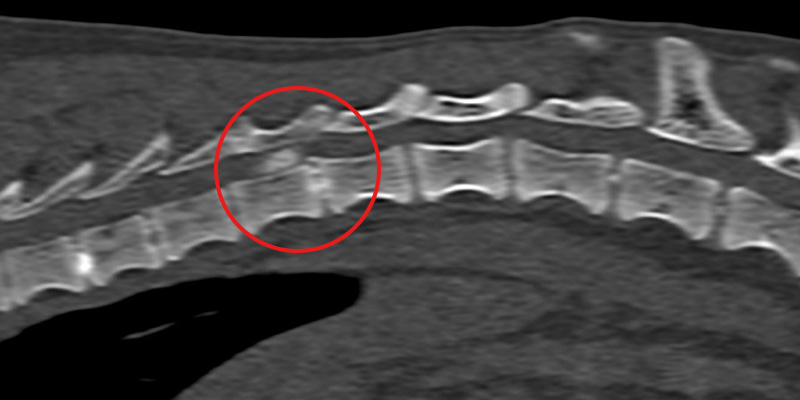

Max’s spine (sagittal view) with compression at T11 highlighted